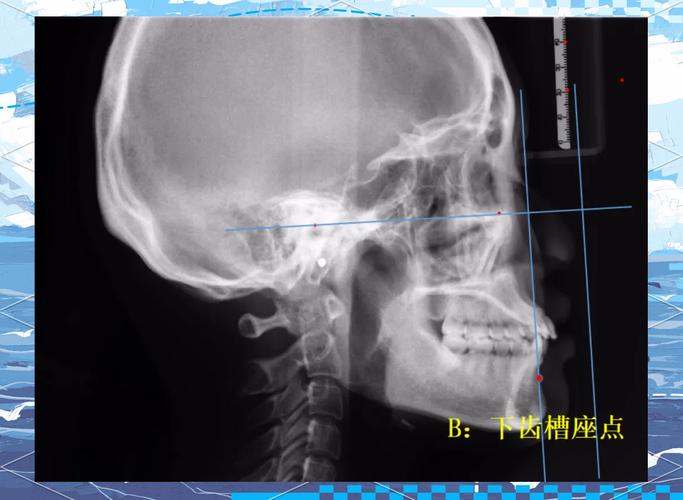

- B点(Supramentale,下齿槽座点):下颌骨前颏联合部与下齿槽缘的交点,位于下颌骨最前端,反映下颌基骨的位置。

- 拍摄标准的头颅侧位X线片,要求患者头颅正中矢状面与地面垂直,眶耳平面与地面平行,避免头位偏斜导致标志点定位误差。

- 在X线片上精确标记A、N、B三点:N点通常位于鼻梁根部凹陷处;A点为上颌牙槽突最前点,与上颌中切牙牙根尖接近;B点为下颌牙槽突最前点,与下颌中切牙牙根尖接近。

- 连接N-A线(鼻根点至上齿槽座点的连线)和N-B线(鼻根点至下齿槽座点的连线),两条线在N点形成夹角,即为anb角。

- 使用量角器或专业测量软件(如Dolphin、Vceph等)测量夹角大小,通常以度(°)为单位,精确到0.1°。